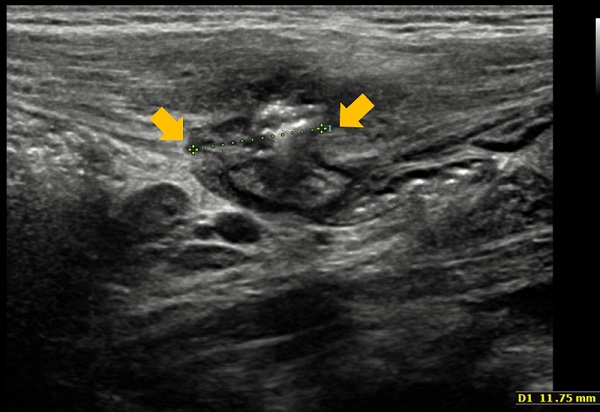

Ante la sospecha de hernia de Spiegel, se pide nueva ecografía orientada, que confirma el diagnóstico (Figs. 1 y 2).

| Figura 1. Ecografía en la que se observa hernia en la pared abdominal derecha con contenido de asas intestinales y grasa mesentérica, con un eje mayor de 29 mm y un orificio de 12 mm |

La dificultad en el diagnóstico conlleva, frecuentemente, un retraso que aumenta la probabilidad de incarceración y cirugía de urgencia, hecho que ocurre en el 21% de los casos2. Para la detección es fundamental la sospecha diagnóstica ante un dolor abdominal atípico y una masa fluctuante que aumenta con la maniobra de Valsalva. La protrusión intermitente de las asas intestinales es la causa del dolor abdominal, hecho que lleva a pensar que, en el caso de este paciente, la “desinvaginación” que refieren los padres probablemente fuera una reducción manual de la hernia.

La ecografía abdominal, prueba complementaria que confirma el diagnóstico, no está exenta de dificultades, debido a que la masa es evanescente. El interior del saco herniario puede estar vacío, pero también puede contener asas intestinales o el testículo ipsilateral, cuando se asocia a criptorquidia. La ecografía Doppler valora si hay estructuras vasculares implicadas.